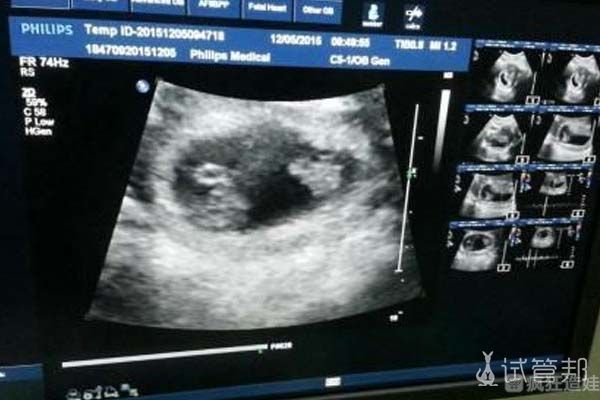

因为我自己的卵巢功能保持良好,一周期的胚胎培养结束后的养囊成绩:养囊8颗,3颗成功过筛。医院的话真的比较干净,而且整体的私密性笔记好,也通过医院找到了合适的孕妈妈,因为老公还是比较喜欢男孩,所以我们最后选择移植的是男孩的胚胎。我们选择的孕妈妈自己也是有2个小孩的,而且她的子宫条件很不错,所以我们也比较放心,着床也成功了,现在都已经3个月了,会定期给我们发一些B超的照片。